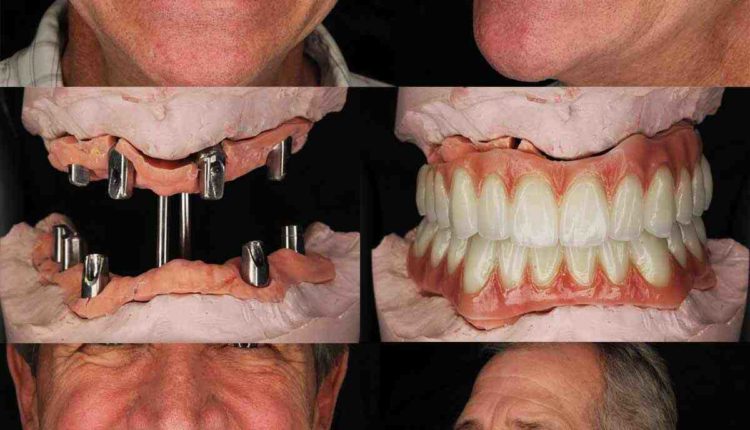

How many implants are needed for full mouth?

How many teeth can one implant hold?

Your dentist can place an implant at each end of the hole. The implants support crowns and the crowns support 1-3 pontics between them. Read also : Dental Implant Procedure Pain. In total, two dental implants can replace up to five teeth in total.

Which is better all on 4 or all on 6 dental implants?

The most obvious difference between all-in-4 and all-in-6 dental implants is the number of implants placed in the mouth. Some dentists believe that the all-in-6 dental treatment provides a stronger, more stable base for the prosthetic dental arch, resulting in a longer lasting and more pleasant smile.